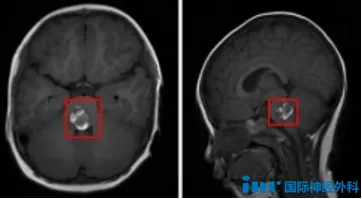

伊伊今年两岁,在某天突然出现了让家人警觉的异常:双眼斜视、眼球不受控制地偏转、行走时明显步态不稳。家人起初将其归咎于眼部问题,带孩子前往眼科就诊。然而头颅影像检查的结果让这个家庭陷入震惊:脑干海绵状血管瘤急性出血。

围绕手术方案,中德联合专家团队进行了充分的术前讨论。病变位于脑干桥脑区域,周围密布重要的神经核团与传导束。手术团队最终确定了损伤最小的入路方式,并针对可能出现的各类突发情况制定了详细预案。

手术由巴特朗菲教授主刀,苏州大学附属儿童医院神经外科团队协同配合。借助高倍手术显微镜和术中电生理监测,巴教授在脑干密集的神经结构中精确识别并保护了"不可触碰"的功能区,先完成血肿清除,再将约2厘米大小的桥脑海绵状血管瘤完整剥离。